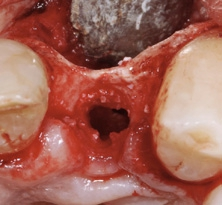

Der chirurgische Eingriff wurde unter Lokalanästhesie mit palatinaler und labialer Infiltration durchgeführt. Zuerst erfolgte die Entfernung des Implantats. Für die Explantation wählten wir das aus unserer Sicht knochenschonendste Verfahren. Mithilfe einer Extraktionszange und mit entsprechend dosierter Kraft drehten wir das teilweise ankylotische Implantat in Achsrichtung aus, um auf jeden Fall die dünne labiale Knochenlamelle zu erhalten (Abb. 3). Dabei frakturierte der osseointegrierte Implantatapex tief im Implantatbett (Abb. 4). Um diesen zu entfernen, musste ein minimalinvasiver apikaler Zugang geschaffen werden. Nach einer krestalen Inzision mit mesialer Tunnelpräparation und distaler Entlastungsinzision sowie der Präparation eines Mukoperiostlappens zeigte sich ein ausgeprägter konkaver Alveolarknochen. Mit einem piezotechnisch unterstützten Chirurgieansatz fenestrierten wir die labiale Knochenlamelle (Abb. 5). Durch diesen minimalinvasiven Zugang lösten wir die ankylotische Verbindung und entfernten den apikalen Implantatrest. Bei dieser Methode der Implantatentfernung wird der periimplantäre krestale Knochen weitestgehend geschont.